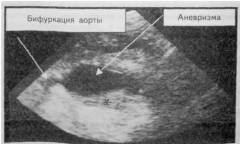

Если по результатам физикального обследования есть основания подозревать аневризму, назначаются инструментальные методы обследования. УЗИ является простым и распространенным методом диагностики аневризмы брюшной аорты.

С помощью УЗИ необходимо получить следующие данные:

Ультразвуковое исследование

Ультразвуковое исследование (УЗИ) — доступный и эффективный метод диагностики аневризмы брюшной аорты. Он основан на отражении звуковых волн от органов и образований в брюшной полости. Специальный датчик фиксирует отраженные волны и создает изображение. УЗИ отличается низкой стоимостью и высокой информативностью, позволяя квалифицированному специалисту обнаружить даже небольшие аневризмы. Процедура занимает 10-15 минут и безопасна для пациента.

При проведении УЗИ необходимо получить следующие данные:

- диаметр аорты под диафрагмой;

- диаметр аорты перед бифуркацией;

- диаметр аневризмы (мешковидное или веретенообразное расширение);

- наличие кальцификатов в стенке сосуда;

- место расслоения стенки (если интима отошла на значительном участке).

Также с помощью УЗИ в режиме допплерографии можно оценить скорость кровотока. В области аневризмы она будет снижена. Рекомендуется проверить скорость кровотока в сосудах нижних конечностей для выявления признаков ишемии и других нарушений. Перед операцией измеряют скорость кровотока в почечных артериях и определяют расположение почек и надпочечников.